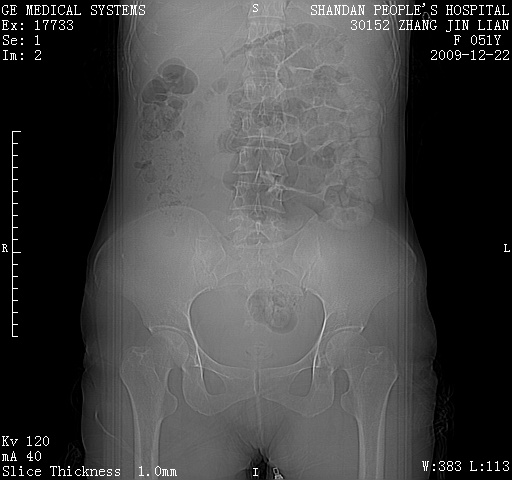

以下是引用zjzjr在2009-12-23 11:28:00的发言:[br]右上部可见大范围实性部份,考虑卵巢囊腺癌可能性大。 [br]盆腔少量积液.

以下是引用卜一在2009-12-23 6:25:00的发言:[br]卵巢囊腺瘤或囊腺癌!